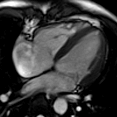

生命感知自由心脏成像平台

MAGNETOM Vida磁共振系统可实现全新的生命感知自由心脏成像:病人进行心脏扫描时,无需配套任何呼吸门控装置,在扫描过程中,磁共振会全程监测病人呼吸以及心电信号,实时控制信号采集;在BioMatrix生命矩阵系统的协助下,Vida可实现业界最快的心脏电影成像,比常规心脏电影成像快10-20倍,可以自由呼吸状态,一个心动周期完成电影采集。

生命感知的自由心脏电影

自由呼吸完成扫描,一个心动周期完成电影采集